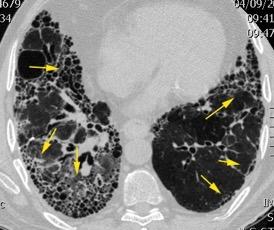

Síndrome antisintetasa

(Miositis anti Jo-1).

Artralgias migratorias, Miositis, “Manos de mecánico”, Raynaud y Enfermedad

intersticial pulmonar (>70%).

Waseda Y et al.. Eur J Radiol. 2016